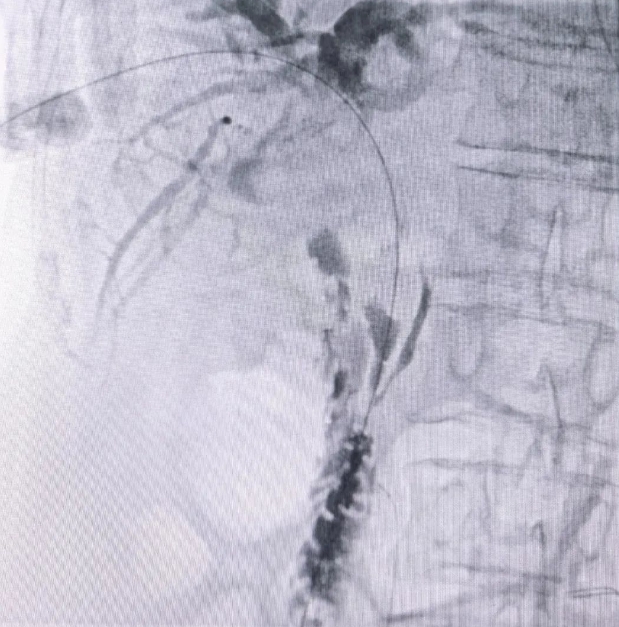

术中,经皮肝穿刺胆道造影。

术中,科室团队以精湛技艺精准定位,直达病灶核心。医护人员紧密协作,成功引流胆汁,手术过程顺利。术后复查显示,患者总胆红素指标显著下降,因胆汁淤积导致的黄疸症状和肝功能损害得到明显改善,为后续治疗赢得了宝贵时间。术后,介入科医护人员还提供了详尽的术后指导和心理疏导,得到了患者及家属的赞扬。